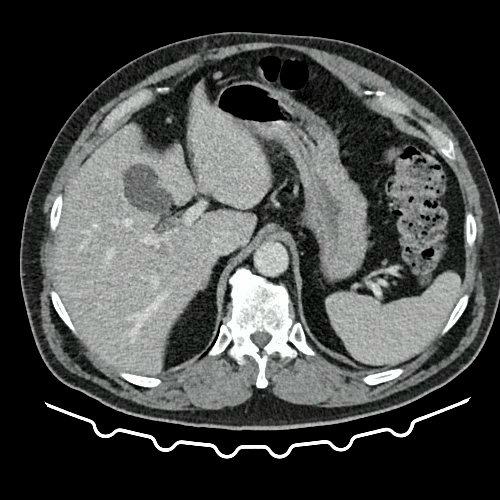

• TAC de abdomen y pelvis con contraste EV (Día 10): El hígado es de forma, tamaño y situación habituales. Su superficie es lisa, y sus bordes son agudos. No presenta alteraciones densitométricas ni efectos de masa focales. La vía biliar intra y extrahepática es de calibre conservado. La vesícula biliar es de forma, tamaño y situación normales, sin imágenes que sugieran la presencia de litiasis. Tener en cuenta que este método puede pasar por alto litiasis colesterínicas. El bazo es de forma, tamaño y situación normales. El eje esplenoportal es de calibre y trayecto conservado. El páncreas es de características normales. El conducto de Wirsung es de calibre conservado. Las glándulas adrenales son normales. Ambos riñones son de forma, tamaño y situación habituales. Sin evidencia de alteraciones calicopiélicas ni ureterales. Quistes simples corticales en riñón izquierdo, el mayor de ellos en polo superior, que mide 16 mm. Discreta reticulación de la grasa perirrenal bilateral. La aorta, las arterias ilíacas primitivas, internas, externas y femorales, son de calibre y trayecto conservado. La vena cava inferior y las venas ilíacas primitivas, internas, externas y femorales son de calibre y trayecto conservados. Filtro de vena cava inferior infrayacente a venas renales. No se observan adenomegalias intraperitoneales, retroperitoneales, ilíacas ni inguinales. No se observan alteraciones a nivel del tracto gastrointestinal. Abundante contenido de materia fecal en el colon. Vejiga con escasa repleción. La próstata y las vesículas seminales son de características normales. No se observa líquido libre ni neumoperitoneo Presenta aumento del diámetro de la raíz del muslo izquierdo con respecto a su contralateral, asociado a edema de los tejidos blandos superficiales. Reticulación de los tejidos blandos de la región inguinal izquierda, de mayor jerarquía que en estudio anterior, con tendencia a coleccionar. Además se observan ganglios locorregionales aumentados en número y tamaño sin alcanzar rango megálico. Se observa inmediatamente infrayacente a los antes mencionado, un área hiperdensa que realza en fase venosa, con centro hipodenso, que mide 2.2 cm x 1.4 cm, ya visualizado en tomografía previa, sin cambios. Calcificaciones en conducto inguinal bilateral. Hidrocele bilateral. Marcados cambios artrodegenerativos de la columna lumbosacra y coxo-femorales.

TAC de tórax, abdomen y pelvis con contraste EV (Día 10) Corte axial